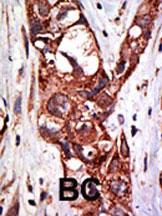

Formalin-fixed and paraffin-embedded human cancer tissue reacted with the primary antibody, which was peroxidase-conjugated to the secondary antibody, followed by DAB staining. This data demonstrates the use of this antibody for immunohistochemistry; clinical relevance has not been evaluated. BC = breast carcinoma; HC = hepatocarcinoma. |